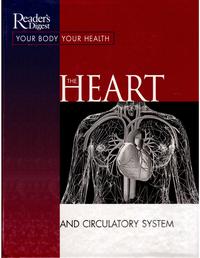

The Alzheimer's Solution |